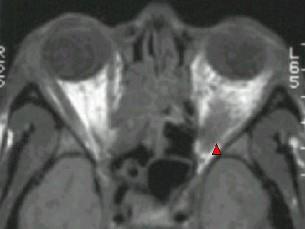

问题 对炎性假瘤(如图)治疗正确的是 ( )

选项 A、必要时手术完整切除防止复发 B、皮质激素用量宜少、短以避免全身并发症 C、一般局部用药效果好 D、放疗最敏感的是淋巴细胞浸润型 E、对皮质激素最敏感的是嗜碱性粒细胞

答案 D